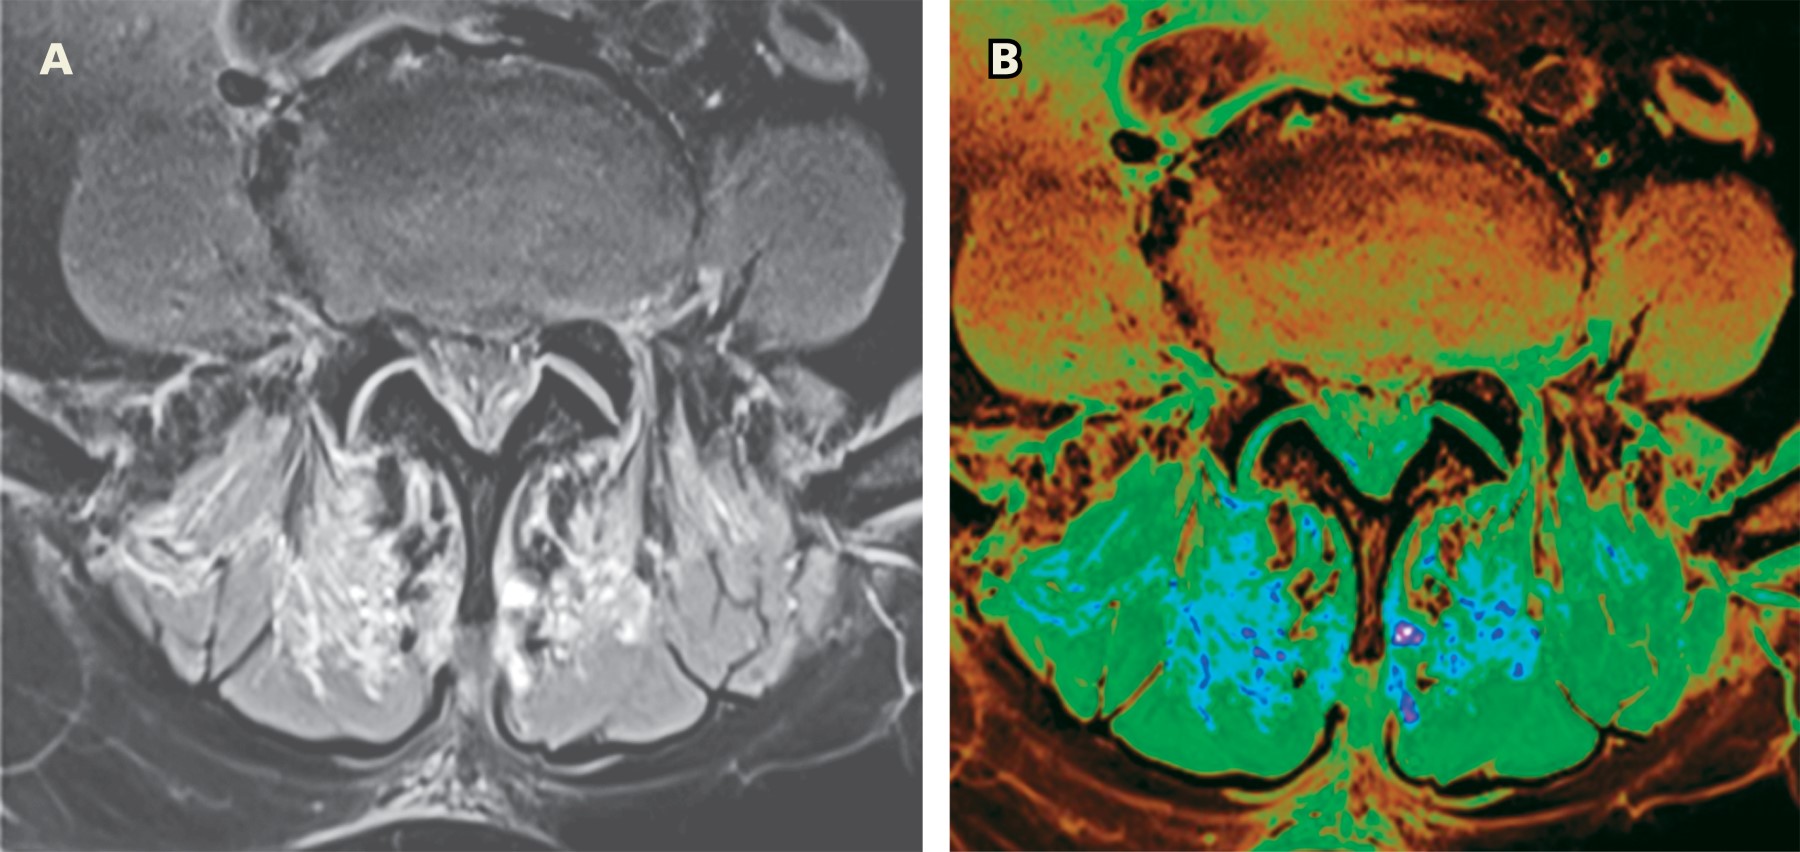

La miositis viral se caracteriza por la presencia de fiebre, anorexia, mialgia y debilidad muscular. Pocos informes han descrito la miositis paraespinal y la miositis complicada con rabdomiólisis como manifestación de la infección por SARS-CoV-2 en adultos. Presentamos el caso de una paciente que desarrolló una miositis paraespinal secundaria a COVID-19, confirmada por resonancia magnética, caracterizada por un edema intramuscular en los músculos paravertebrales. La grave reacción inmunitaria de la COVID-19 y la posterior activación de la tormenta de citoquinas podrían desempeñar un importante papel fisiológico en el daño muscular. Por lo tanto, en esta pandemia, los clínicos deberían considerar la miositis o la rabdomiólisis como diagnóstico diferencial en pacientes con dolor muscular focal y fatiga.

Figura 1

Figura 2